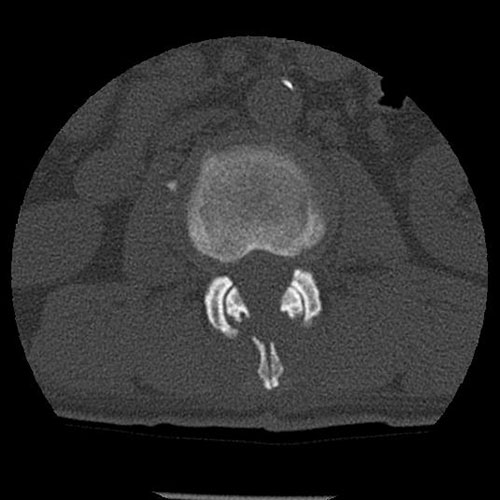

背骨のレントゲンを撮ったり、MRIやCTを撮影したりします。

身体所見とこれらの画像を使って、どこで神経を圧迫しているのかを診断します。